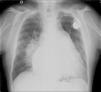

The electrocardiogram showed atrial fibrillation with ventricular response of 55 bpm, right bundle branch block and left posterior hemiblock. The chest X-ray after pacemaker implantation (Figure 3) showed a cardiothoracic ratio of >50%, dilatation of the right atrium and of both pulmonary arteries, and pulmonary vasculature enhancement. The transthoracic echocardiogram showed a dilated left atrium; interventricular septal hypertrophy, with preserved left ventricular function, and dilated right chambers with annular dilation of the tricuspid valve, causing moderate tricuspid valve regurgitation, with pulmonary artery systolic pressure calculated at 50 mmHg (moderate pulmonary hypertension); and a dilated pulmonary artery and mild pulmonary regurgitation. No morphological defect of the atrial septum was found, or flow across the atrial septum; the ventricular septum also showed no morphological defect.

Chest X-ray may show enlarged pulmonary arteries due to pulmonary hypertension or cardiomegaly and evidence of congestive heart failure may be present.